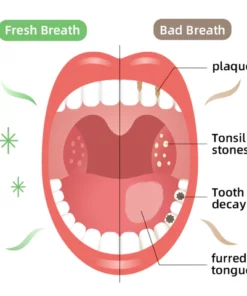

What Causes Poor Oral Health?

Every day, food residues in our mouths create a breeding ground for various bacteria and microorganisms within the oral cavity. This can result in a range of oral health issues, including bad breath, mouth ulcers, yellow teeth, cavities, calculus buildup, gum inflammation, bleeding gums, tooth sensitivity, weakened or missing teeth, swollen gums, toothaches, loose teeth, tooth loss, and even the risk of oral cancer.

As these conditions worsen, you may experience persistent bad breath, gum inflammation, and other problems. Bacteria continue to harm your gums, leading to issues like bleeding, pain, and redness. Without timely intervention, these oral problems can escalate, potentially causing periodontitis, dental plaque, dental calculus, loose teeth, tooth pain, and eventually tooth loss.

Dental caries develop when germs damage tooth enamel and gradually penetrate into the dentin and even the pulp. This can result in bad breath, toothaches, weakened teeth, and potential tooth loss. The presence of caries often triggers a chain reaction, causing healthy teeth to be affected as germs spread to adjacent teeth.